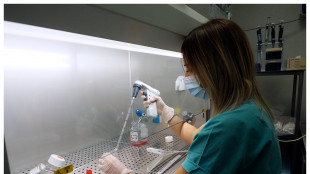

Così le cellule reprimono i resti di antichi virus nel Dna

Scoperta utile contro tumori e disturbi neurologici

Bioplast, ricostruire ossa e cartilagini dalle cellule staminali

Ricerche nel laboratorio di ricerca del Policlinico di Palermo